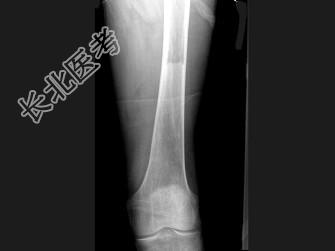

- 单项选择题男,60岁, 左股骨痛1年余,结合图像, 最可能的诊断是 ( )

A、骨纤维异常增殖症

B、Paget病

C、髋关节结核

D、股骨头缺血坏死

E、化脓性骨髓炎